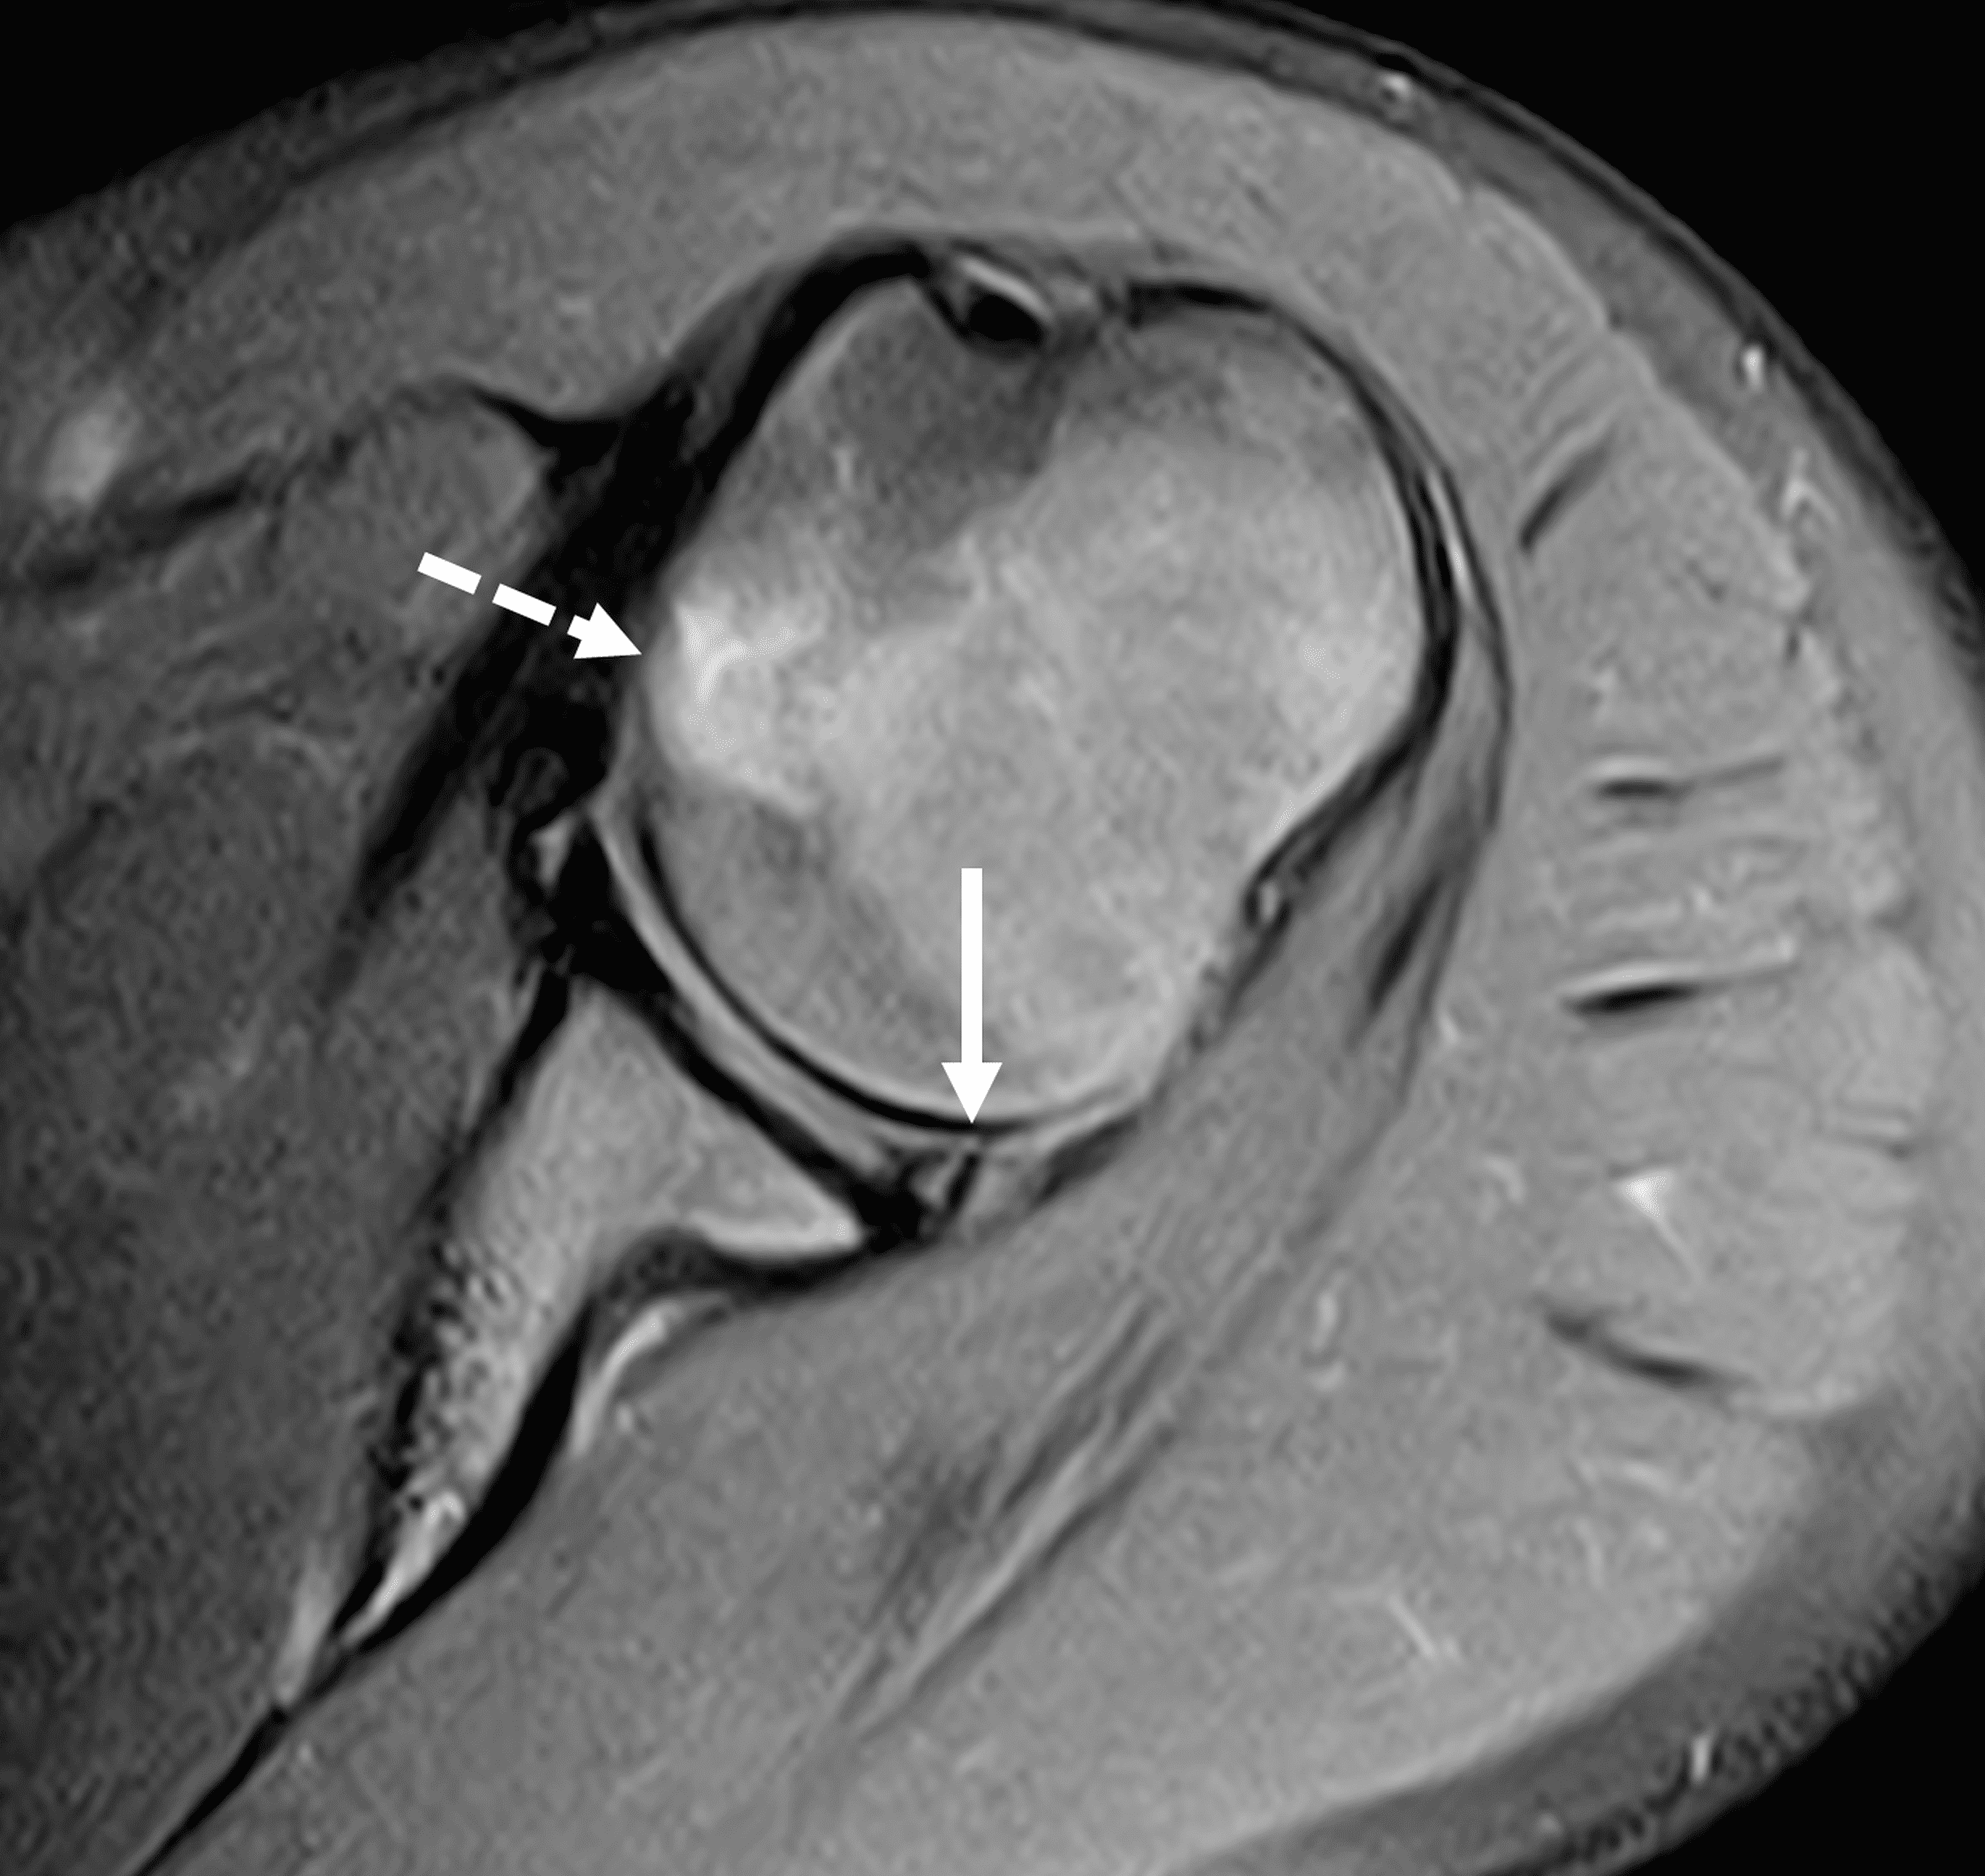

Figure 3: 18 year-old-female college softball player with acute left shoulder batting injury. (3A and 3B) Axial fat-suppressed proton-density-weighted images show a nondisplaced intrasubstance posteroinferior labral tear (solid arrows) and anteromedial humeral head impaction fracture with mild underlying marrow edema (dashed arrows).